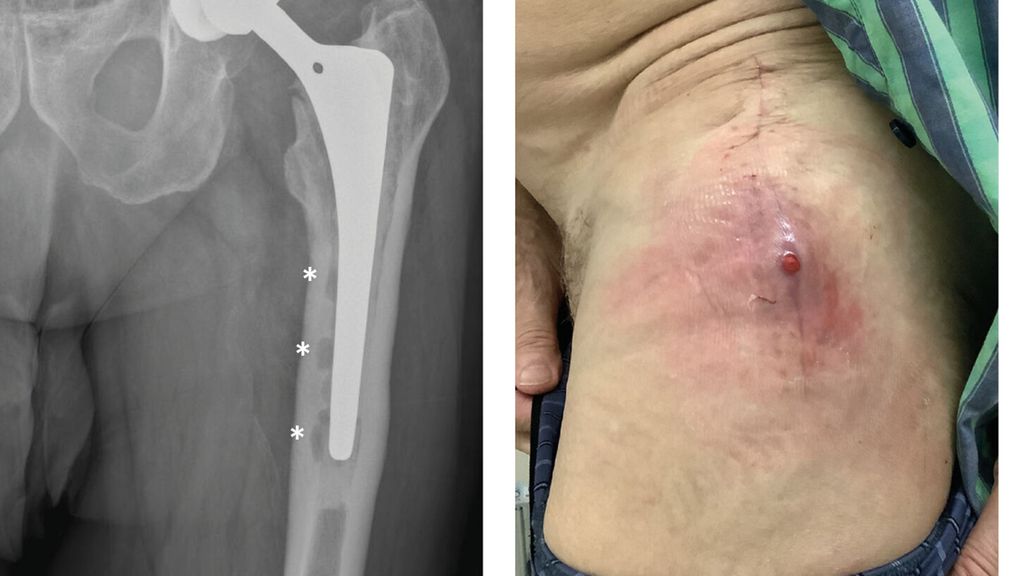

Anhand der klinischen Zeichen und der Symptomdauer unterscheidet man zwischen akuter und chronischer PPI. Die akute PPI ist durch eine kurze Symptomdauer (<3 Wochen) charakterisiert. Sie tritt entweder in der frühen (<4 Wochen) Phase nach endoprothetischem Gelenkersatz (akute postoperative PPI) oder aber verzögert (>4 Wochen, ggf. erst mehrere Jahre) nach Endoprothesenimplantation im Rahmen einer hämatogenen Streuung eines endoprothesenfernen Infektionsherdes (akute hämatogene PPI) auf. Typischerweise imponieren hier lokale Infektionszeichen wie Schmerzen, Schwellung, Rötung, Überwärmung oder eine prolongierte Wundsekretion (>7 Tage). Die Unterscheidung zwischen akuter und chronischer PPI basiert auf den Eigenschaften des bakteriellen Biofilms. Beim Vorliegen einer akuten PPI ist von einem unreifen bakteriellen Biofilm auf der Endoprothesenoberfläche auszugehen. Bei der chronischen PPI (>4 Wochen postoperativ) mit längerer Symptomdauer (>3 Wochen) liegt hingegen ein potenziell reifer Biofilm vor. Die klinischen Symptome sind in der Regel weniger ausgeprägt. Jedoch kann das Vorliegen einer kutanen Fistel oder von radiologischen Zeichen der Endoprothesenlockerung auf eine chronische Infektion hinweisen (z. B. Abb. 1).